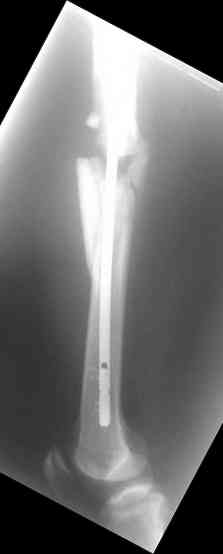

Надеюсь сейчас показать перелом, а потом синтез.

Вложение не в текстовом формате было извлечено…

Имя     : 3.jpg

Тип     : image/jpeg

Размер  : 5294 байтов

Описание: отсутствует

Url     : http://weborto.net:8080/pipermail/ortho/attachments/20070925/7aabe9cf/attachment-0007.jpg